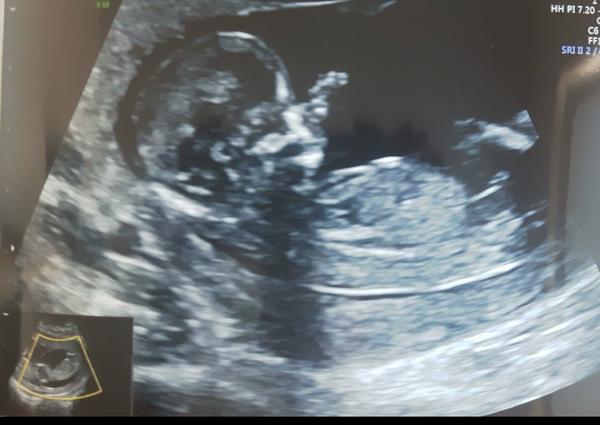

jsem na webu poprvé a hned mám otázku. Poznáte z ultrazvuku jaká budeme mít pohlaví? Jsem v 13tt a čekáme dvojvaječná dvojčátka- takže kombina jakákoliv 😀. Dneska mi paní doktorka sdělila co vidí, ale nebyla si úplně jistá 😀 proto bych chtěla znát vás názor co si myslíte vy.

Druhé foto v komentáři 😉